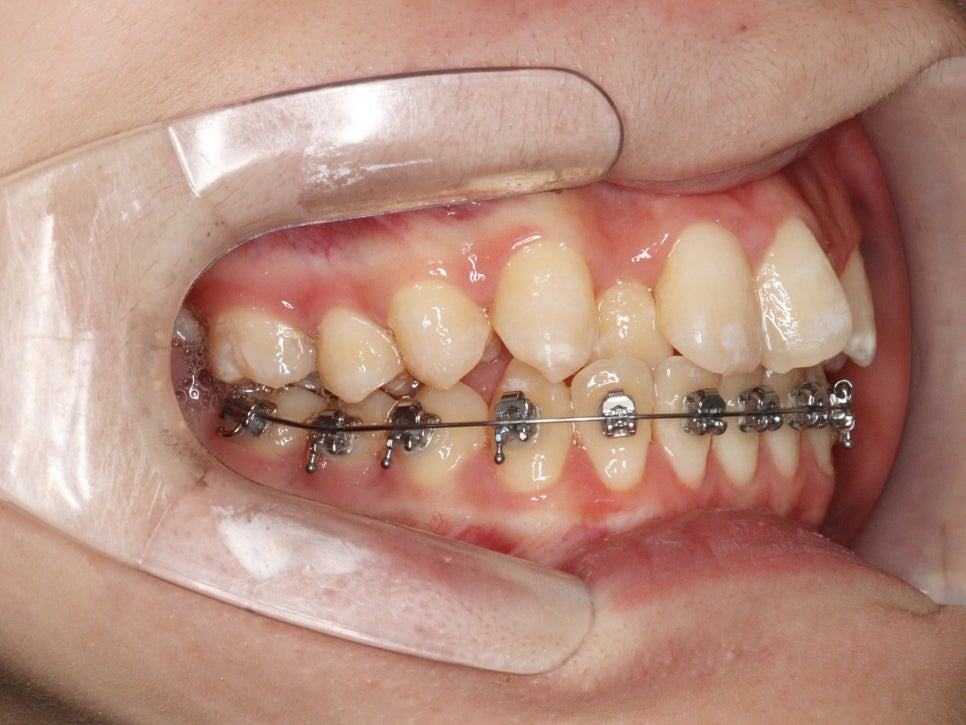

위와 같이 삐뚤삐뚤했던 치열을 가진 아이가 와서 #철사교정 치료를 하고

마무리가 되었습니다.

이 아이는 치료를 위해 #악궁확장 장치도 4개월간 사용하였습니다.

악궁확장장치의 사용까지 필요했던 아이로, 전체 치료기간이 조금 긴 느낌입니다.

2022.4.26. ~ 2024.5.27.

약 2년1개월이 소요되었네요